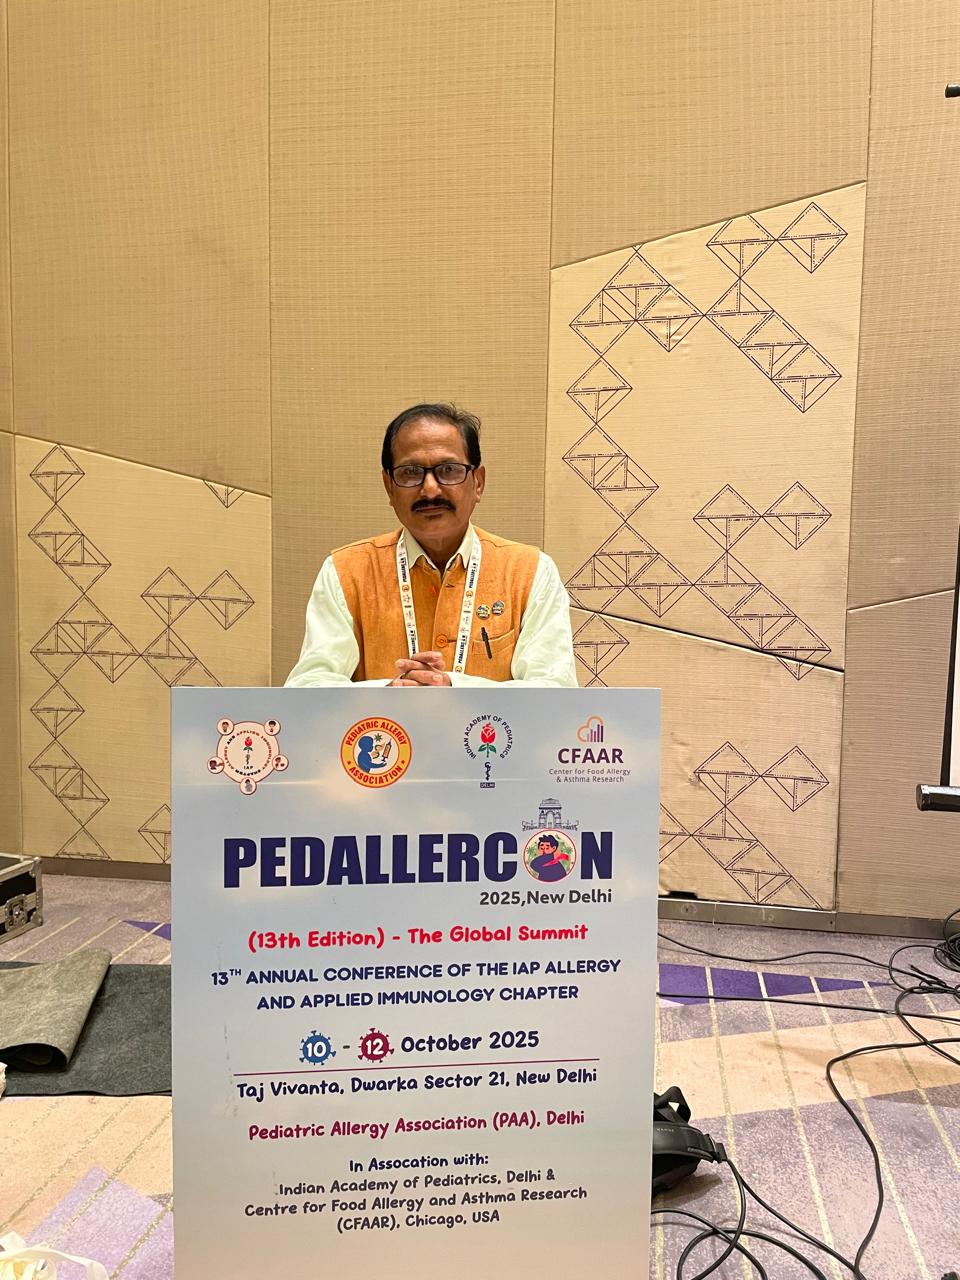

Welcome to the Bengal Allergy and Asthma Centre.We are certified specialists in Allergy and Clinical Immunology and have academic appointments . Our clinic provides comprehensive Allergy services for both children and adults.We manage the full range of allergic disorders, including food allergy, environmental allergy, anaphylaxis, stinging insect allergy, medication allergy, asthma, hives, and angioedema. Diagnostic allergy testing utilizes modern techniques that are gentle and well-tolerated. There is a strong focus on accurate diagnosis and personalized treatments based on medical evidence and experienced clinical judgment.